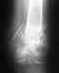

Добрый день! 11 января 2013 года случилась травма - перелом лодыжки. Четыре недели носила гипс, затем была выписана, так как на рентгене перелом выглядел как сросшийся. Нога продолжала болеть, 26 апреля МРТ определила несросшийся перелом латеральной лодыжки со скрелозированными контрурами смежных поверхностей, без смещения. вопрос: возможно ли консервативное лечение? Живу Екатеринбурге, возможно ли записаться на консультацию? Возможна ли помощь в рамках ОМС? Спасибо!

Без осмотра и снимков ситуация непонятна. Можно прийти на консультацию к нам - Московская, 12, пнд-чтв, 9-14 ч. С собой все справки-снимки, паспорт, полис ОМС.